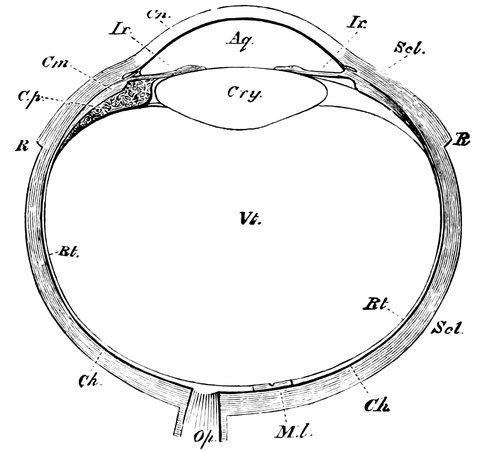

| 32. | Horizontal section of the eyeball | 66 |

| 33. | Action of eye in formation of images | 68 |

| 34. | Action of a long-sighted eye | 69 |

| 35. | Diagram showing path of rays when viewing an object at an easy distance | 70 |

| 36. | Action of short-sighted eye | 71 |